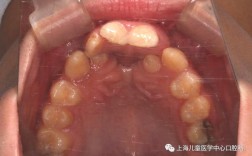

唇腭裂患者的口腔颌面特点具有复杂性,其畸形程度可分为单侧完全性唇腭裂、双侧完全性唇腭裂、不完全性唇腭裂等多种类型,不同类型的畸形表现差异较大,典型问题包括:牙弓狭窄呈“V”形,上颌骨发育不足导致面中部凹陷,牙齿萌出位置异常(如腭侧萌出、颊侧萌出),牙列拥挤或稀疏,前牙反颌(俗称“地包天”),后牙反颌及锁颌,以及因裂隙存在导致的缺牙或多生牙等,这些问题不仅影响咀嚼、发音功能,还会对患儿的心理发育造成负面影响,因此早期干预和系统性正畸治疗至关重要。

口腔正畸治疗在唇腭裂序列治疗中需分阶段进行,根据患儿不同年龄段的颌骨发育和牙齿替换特点制定个性化方案,术前正畸通常在患儿3-6个月龄时开始,主要针对完全性唇腭裂患儿,通过佩戴活动矫治器(如Hotz矫治器、Latham矫治器)将两侧裂隙的牙弓段向中线聚拢,缩小裂隙宽度,为唇裂修复术创造有利条件,同时改善牙弓形态,防止舌体压迫导致牙弓进一步狭窄,术后正畸一般在唇腭裂修复术后3-6个月开始,此时创口已愈合,主要目标为调整牙弓形态,纠正反颌、开颌等错颌畸形,促进牙弓对称性发育,对于混合牙列期患儿,重点在于管理间隙,利用缺牙间隙维持牙弓长度,引导恒牙正常萌出;恒牙列期则需通过固定矫治器(如方丝弓矫治器、直丝弓矫治器)进行全面的牙齿排齐、整平牙弓、纠正咬合关系,部分严重上颌骨发育不足的患儿需配合前方牵引等骨性矫形治疗,成年后,部分患者可能还需结合正颌外科手术,通过正畸-正颌联合治疗改善颌骨关系,达到功能与美观的统一。